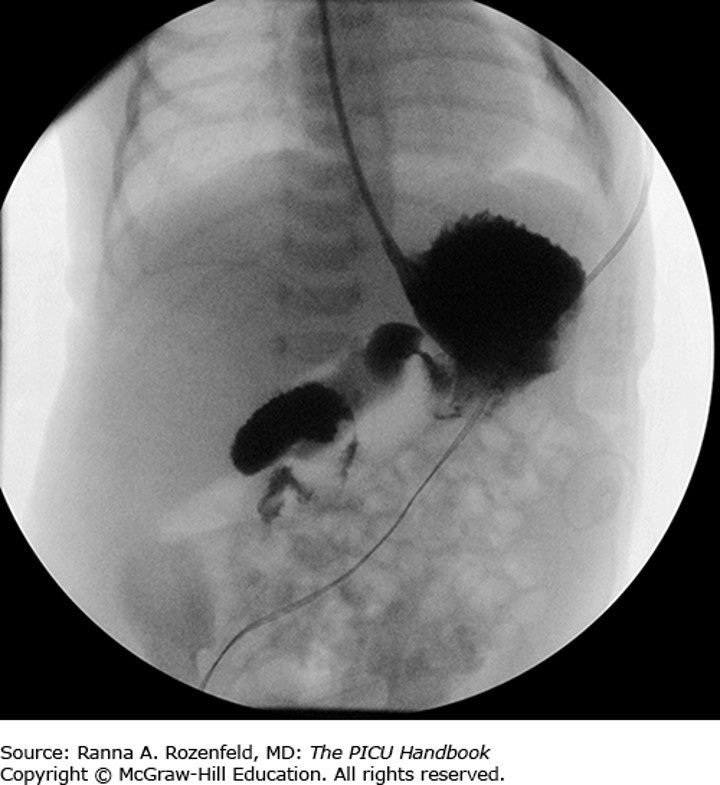

The correct answer is “B.” This infant has malrotation with volvulus—a surgical emergency. Rotational anomalies may become symptomatic at any age; however, more than 80% present in the first month of life, often in the first week. Risk of acute volvulus is highest in the neonatal period. In malrotation, the intestine fails to rotate in utero and fixate in the correct position. It is adhered by a narrow pedicle of mesentery, which allows the intestine to twist around itself. The cecum ends up in the right upper quadrant. The risk is volvulus, most often at midgut. This occurs when the intestine strangulates by twisting, cutting off the blood supply and blocking the flow of fecal contents and gas through the tract. Bad outcomes (perforation, infarction) ensue if it is not surgically corrected. (You may have heard the term Ladd bands used. These are tissue bands that cross and obstruct the duodenum). Any infant who presents with bilious emesis is an emergency case. There is also an atypical presentation. (Are you surprised?) Intermittent twisting with pain and vomiting may occur in older children. It is frequently misdiagnosed as cyclic vomiting.

Photo: Chapter 64 GI Emergencies, Rozenfeld RA. The PICU Handbook; 2018.